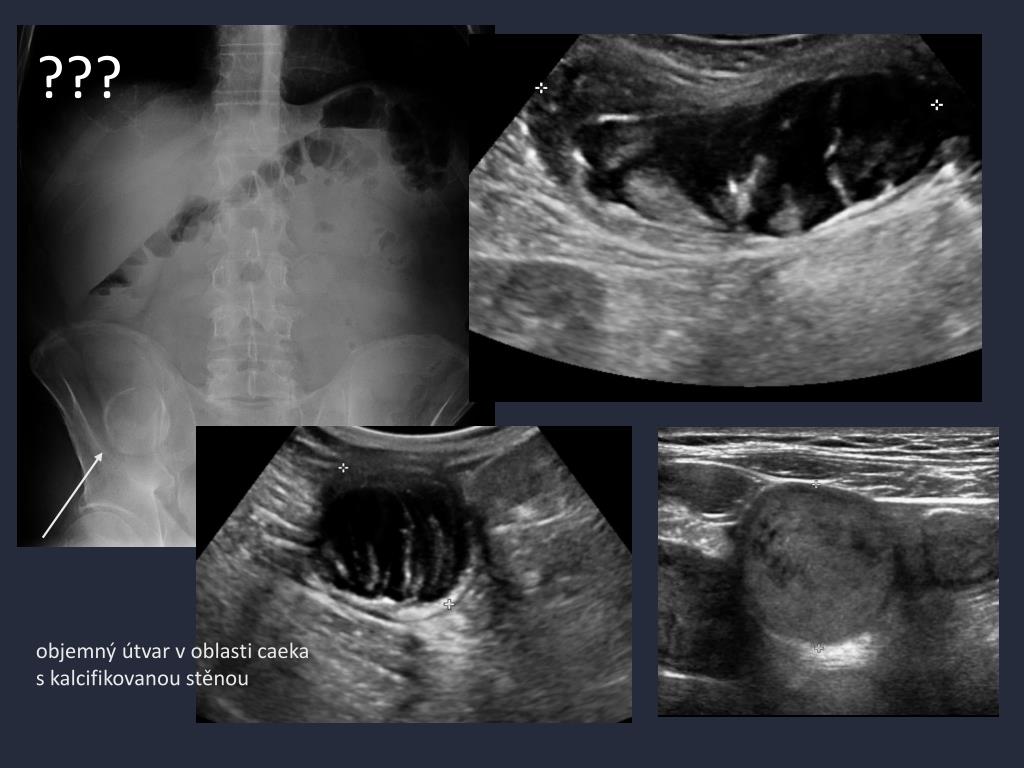

12. ??? objemný útvar v oblasti caeka s kalcifikovanou stěnou

13. dle CT tubulární formace bez akutních zánětlivých změn v okolí • chronicky zánětlivě změněný appendix s patol. obsahem, s kalcifikovaným cystoidem ?